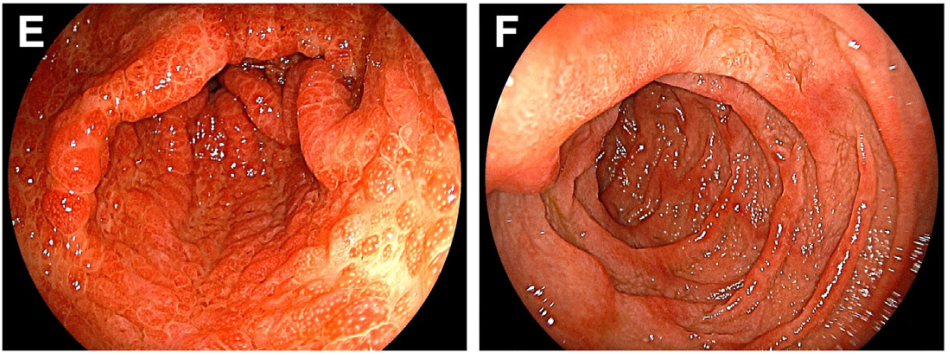

造血干细胞移植术后腹痛+黏液血便:这个极易误诊的肠道“隐形杀手”,千万别忽视!

病史摘要:患者为 36 岁男性,主诉持续性腹痛 5 个月,伴黏液血便 1 个月,后进展为不完全性肠梗阻。3 年前确诊急性 B 淋巴细胞白血病,并行异基因造血干细胞移植,移植后发生累及口腔及皮肤的急性移植物抗宿主病,使用环孢素、芦可替尼治疗至腹痛发作。 诊疗过程:实验室检查示 D - 二聚体及超敏 C 反应蛋白升高,其余正常。结肠镜见乙状结肠及直肠黏膜充血等改变,CT